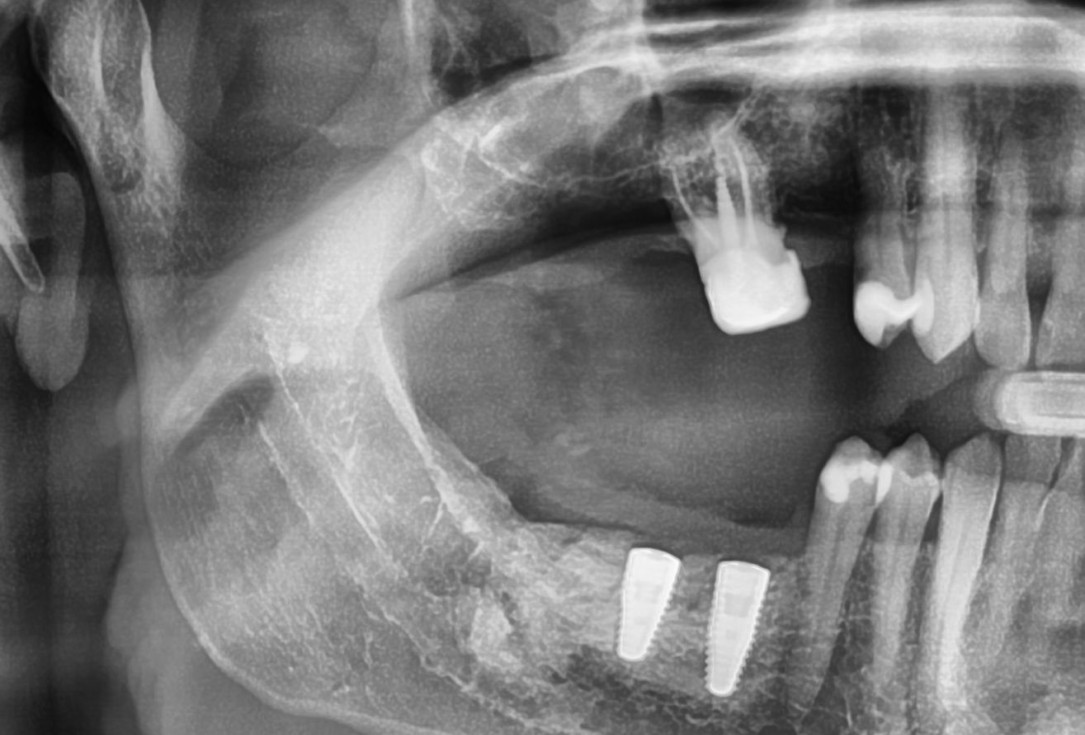

21/28 - X-ray scan of the augmented ridge after implantationThree-dimensional augmentation with maxgraft® cortico - Dr. R. Würdinger